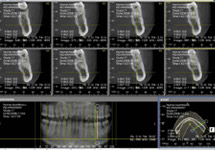

当院では、診断のため歯科用CTを導入しています。

保険診療においても給付適応範囲が広がり、さまざまな疾病を3次元的に精査することにより診断精度が上がってきています。

それにより、当院での治療精度を上げることが可能となってきております。

一方、難症例の見極めも可能となり、患者様にとっての利点が非常に大きいところとなっております。

また、インプラント治療においても骨の形態を3次元でとらえることによりそのデータをさらに解析ソフトにかけることにより、予期せぬ事態が容易に予期でき対応できるようになってきています。